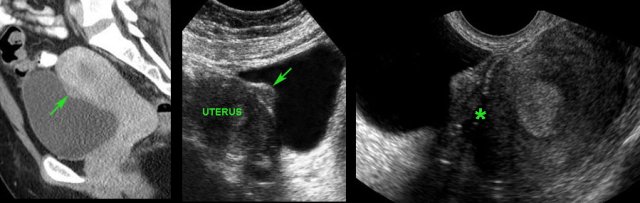

Coincidental finding of “bladder polyp” (arrow) on CT scan in young female.

Confirmation of a flat polypoid structure (arrow) by abdominal US.

Cystoscopy was completely normal, indicating that the mass is covered by normal bladder mucosa..

TVUS  demonstrates that the mass in fact is an endometriotic implant and shows blurring of the hyperechoic contour (*) of the uterus, indicating local ingrowth.

TVUS also demonstrated DIE in Douglas pouch (not shown here).

A 45-year old woman with a long history of painful micturition. Cystoscopy was negative.

CT shows a plaque-like, irregularly defined mass (arrow).

TVUS confirms a large endometriotic implant (arrow) in the prevesical space (cavum Retzii). Note again the ill-defined border with the uterus.